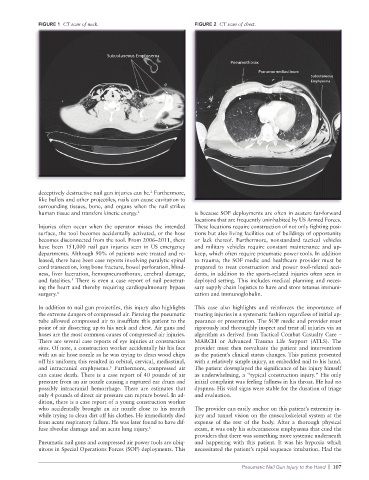

FIGURE 1 CT scan of neck. FIGURE 2 CT scan of chest.